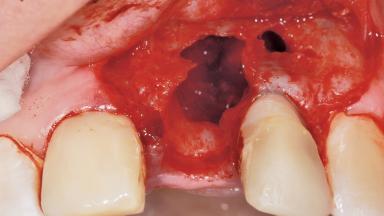

Late Flapless Placement of an Implant in a Maxillary Left Central Incisor Site

A 39-year-old male patient presented with a chief complaint of discomfort and gingival discoloration around his maxillary left central incisor. He was in good general health and was a non-smoker. His past dental history was significant because of the traumatic fracture of tooth 21 in a sporting accident at age 13. Initial dental treatment included endodontic therapy and a full-coverage restoration. The patient became symptomatic 5 years later, when structural failure of the tooth resulted in the dislodgment of the crown. Endodontic retreatment, apical surgery, and post-and-core restoration were performed.